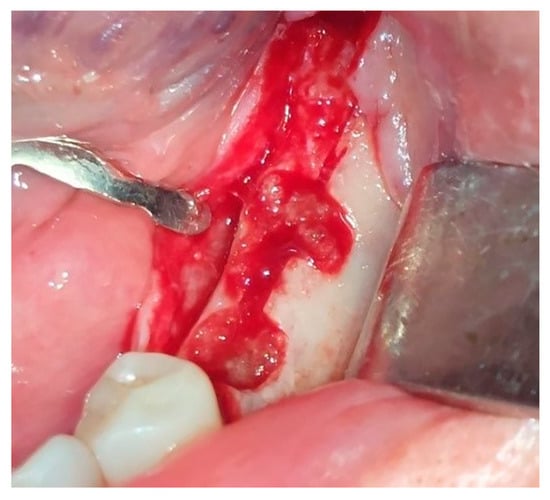

Local anesthesia using 4% articaine with adrenaline 1:100,000 (Septanest®, Septodont, Saint-Maur-des-Fossés, France) was administered. After the midcrestal longitudinal incision, a full thickness mucoperiosteal flap without a vertical releasing incision was elevated and the top of the alveolar ridge was flattened to the width of 4 mm (Figure 3). Preparation of the implant bed was performed with only one twist drill from the set (Esset kit®, Osstem, Seoul, Republic of Korea) which corresponded to the implant length (Figure 4). Following the preparation of the implant bed with the twist drill, a midcrestal longitudinal osteotomy was performed with a special saw with the speed of 1200 rpm (Figure 5). A specially designed set of expanders (Esset kit®, Osstem, Seoul, Republic of Korea) was used gradually in order to separate the buccal plate from the lingual cortical plate, according to their elasticity (Figure 6A–C).

Figure 5. Midcrestal osteotomy with a saw.